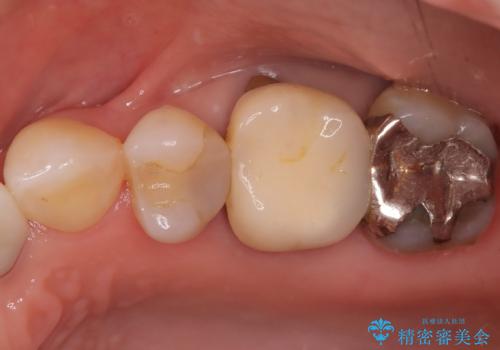

- 「以前治療した被せ物の色が気になる」「最近しみるようになった」との主訴で来院されました。診察の結果、古い被せ物の周囲に段差ができており、そこから虫歯が進行している状態でした。また、色も経年劣化により周囲の歯と調和が取れておらず、笑ったときに目立つとのお悩みもありました。

被せ物の下の虫歯を除去し、必要に応じて土台の補強を行ったうえで、見た目が自然で長期的な安定性もあるセラミッククラウンによる修復をご提案しました。見た目と機能の両方を改善するため、隣接する歯との色調や形態のバランスも考慮した治療計画を立てました。

まず古い被せ物を慎重に取り除き、中に広がっていた虫歯を丁寧に除去しました。歯質の状態を確認したうえで、必要な部分には土台(コア)を補強し、セラミッククラウンを装着する準備を整えました。

最終的な被せ物には、周囲の歯と自然になじむような色合い・透明感を持つセラミックを採用。形も元の歯に近づけ、違和感のない見た目と噛み心地を再現しました。